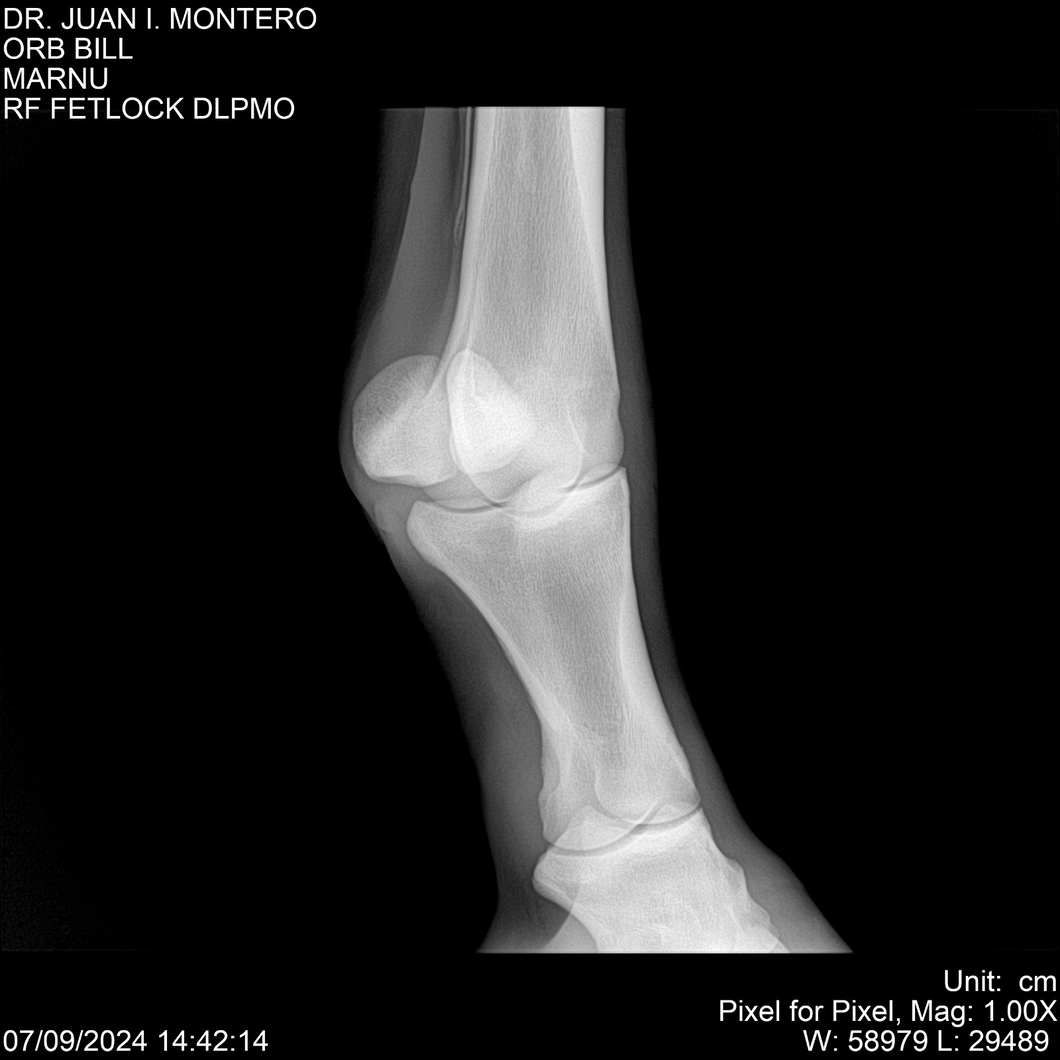

LOTE 7, ORB BILL 🔥 🔥 🔥 Lote Anterior Volver al remate Lote Siguiente Ficha Contacto Montevideo - Ficha del Lote Identificador: #282523 Categoría: Yeguarizos Montevideo - 83 Visualizaciones ClicData Contacto Empresa: Abelenda N. R., Walter Hugo Nombre*: Teléfono* : E-mail* : Mensaje Enviar Registrese gratis Este contenido Exclusivo está disponible sólo para usuarios registrados Ingresar